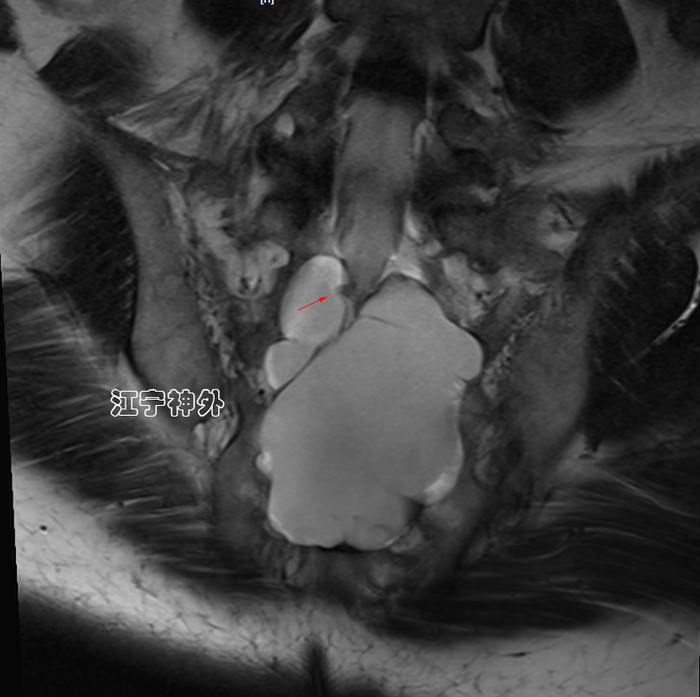

我院术前磁共振检查发现,骶1-3两个巨大骶管囊肿,其中左侧骶管囊肿更大,但症状却是在右侧。

郑主任仔细阅片发现,右侧骶管囊肿虽然比较小,但是其脑脊液漏口处(囊颈)存在一块灰色异常信号,推测可能存在神经根内疝。